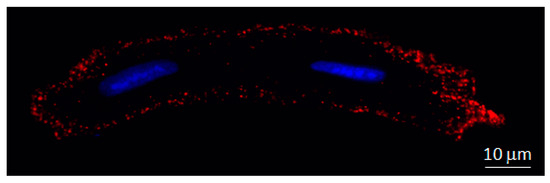

Presence of Cx43 at Cardiomyocyte Mitochondria